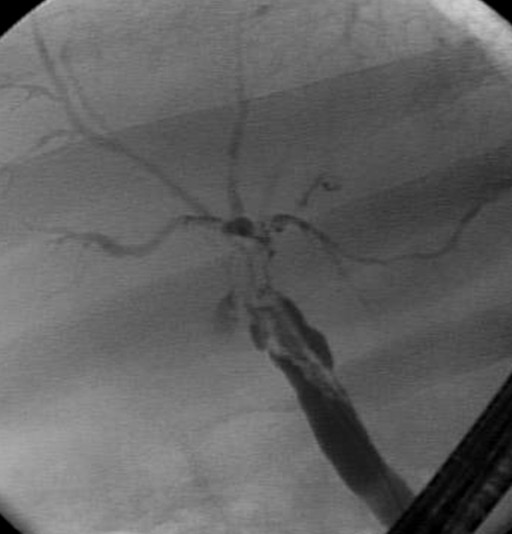

A 68-year-old male with history of orthotopic liver transplantation seven months before for hepatitis C induced cirrhosis presented for a routine follow-up visit. The patient did not report any complaints and physical exam was normal. Routine laboratory evaluation revealed a cholestatic liver enzyme elevation (alkaline phosphatase 580 IU/L, reference range: 80-130 IU/L), total bilirubin 2.3 mg/dL (reference range: 0.7-1.2 mg/dL) with normal aminotransferases and normal prothrombin time. Hepatitis C RNA was undetectable. Ultrasound demonstrated normal common bile duct (C) diameter with normal Doppler flow. Liver biopsy showed no acute rejection, but with suggestion of cholestasis. Endoscopic retrograde cholangiopancreatography (ERCP) with occlusion cholangiogram showed multiple linear filing defects in the proximal hepatic duct proximal to the anastomosis with extension into the intrahepatic system (Figure 1). Balloon failed to remove the filling defect. A single operator choledochoscope was then passed into the common hepatic duct for diagnostic visualization and possible therapeutic purpose. A dark brown tubular structure was seen resembling a cast of the bile duct (Figure 2). Using a basket, the distal aspect of the cast was secured and a 6 cm long cast was successfully removed in a single piece (Figure 3). Cholangiogram showed improvement with excellent biliary drainage both fluoroscopically and endoscopically. Liver function tests subsequently normalized. Patient followed up to a period of 14 months without recurrence of symptoms.

Figure 1. Cholangiogram showing the filling defect. |